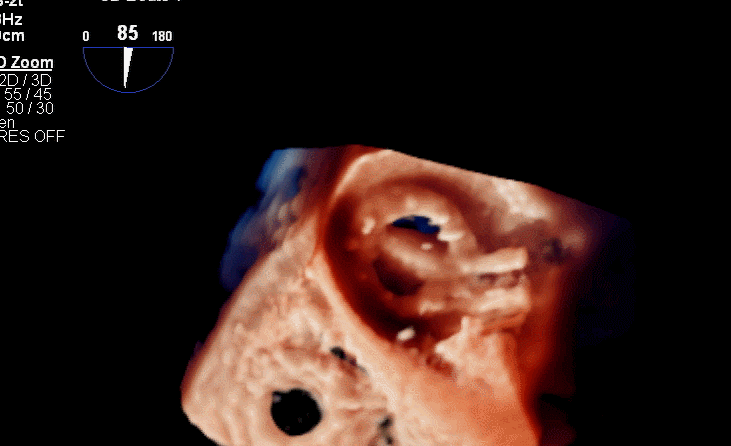

食道超声评估

三尖瓣术前平均压差9mmHg

三尖瓣瓣中瓣术后平均压差3mmHg

术后三维超声同时显示MV机械瓣及新的TV生物瓣